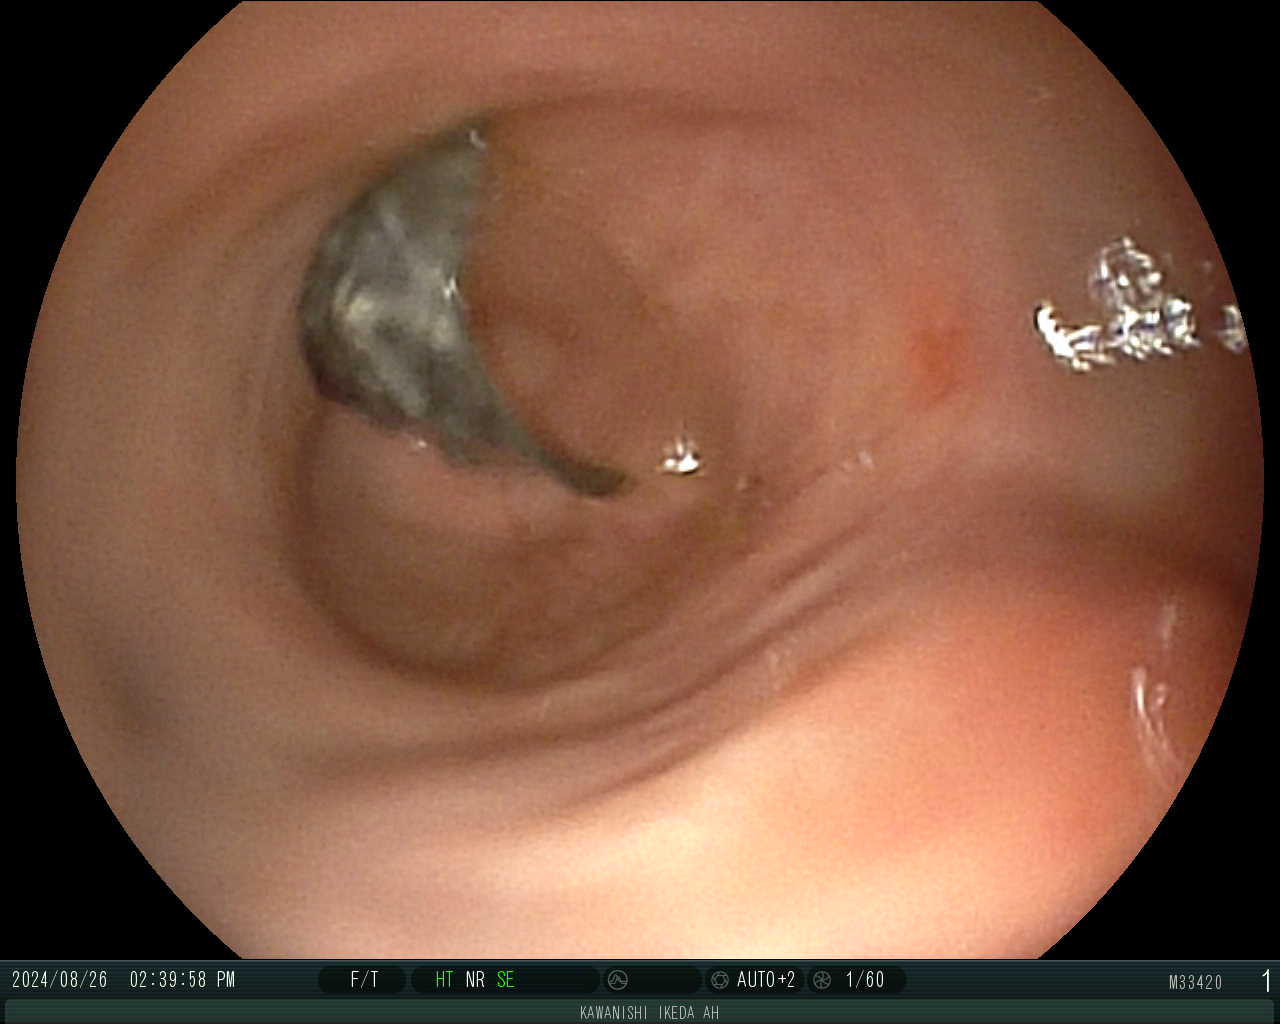

消化管内視鏡による異物摘出

2024/09/06